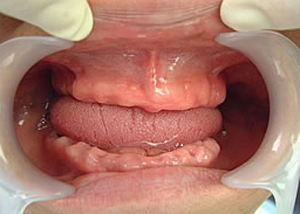

症例4 57歳女性

治療前

(下11本、上1本抜歯済み)

1.下11本、上1本抜歯、同時に総義歯セット